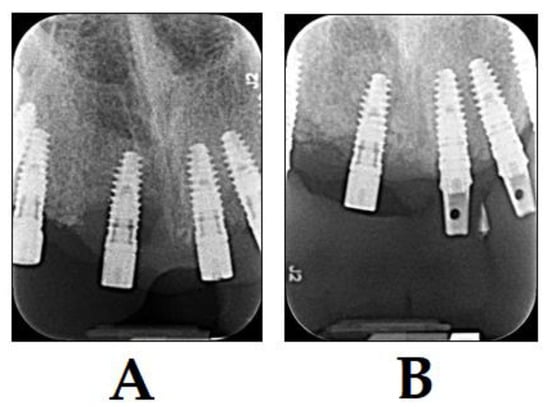

3.5. PDT in Implantology

- Dörtbudak, O.; Haas, R.; Bernhart, T.; Mailath-Pokorny, G. Lethal photosensitization for decontamination of implant surfaces in the treatment of peri-implantitis. Clin. Oral Implants Res. 2001, 12, 104–108. [Google Scholar] [CrossRef]

- Sivaramakrishnan, G.; Sridharan, K. Photodynamic therapy for the treatment of peri-implant diseases: A network meta-analysis of randomized controlled trials. Photodiagnosis Photodyn. Ther. 2018, 21, 1–9. [Google Scholar] [CrossRef]

- Esposito, M.; Grusovin, M.G.; De Angelis, N.; Camurati, A.; Campailla, M.; Felice, P. The adjunctive use of light-activated disinfection (LAD) with FotoSan is ineffective in the treatment of peri-implantitis: 1-year results from a multicentre pragmatic randomised controlled trial. Eur. J. Oral. Implantol. 2013, 6, 109–119. [Google Scholar]